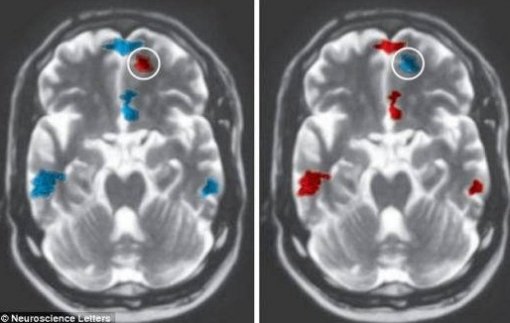

보도에 따르면 공개된 사진 속 좌측이 3년 이상 사귄 사람, 우측이 그렇지 않은 사람의 뇌 스캔 이미지이다.

붉은색으로 나타난 부분이 활발한 움직임을 보이는 곳이며 푸른색은 그 반대를 나타낸다.

보도에 따르면 사람의 뇌를 스캔했을 때 오래 사귄 연인들은 쾌감 중추가 덜 활동적이었다고 전했다.

또한 시각적인 아름다움과 감정적 반응을 보이는 부분이 활동적인 반면, 비판이나 사리 판단에 관련된 부분은 비활동적인 것으로 나타났다.